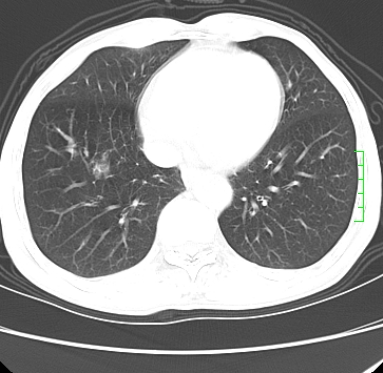

m,73y。膝关节疼痛伴双下肢水肿。入院常规胸片发现结节灶。增强为静脉期。

浅分叶、棘突,考虑右下肺周围型肺癌

考虑周围型肺癌  ,双上肺结核。

肿块周围可见局限性气肿,考虑肺癌可能性大。双肺上叶继发型肺结核。

指套征,强化明显,近侧肺组织局限性肺气肿,考虑支气管类癌,慢支、肺气肿、双上陈旧性tb、冠脉钙化。

1)考虑右肺下叶周围型肺癌。2)右肺上叶及左肺感染性病变(结核可能)。3)肺气肿。4)冠状动脉钙化。